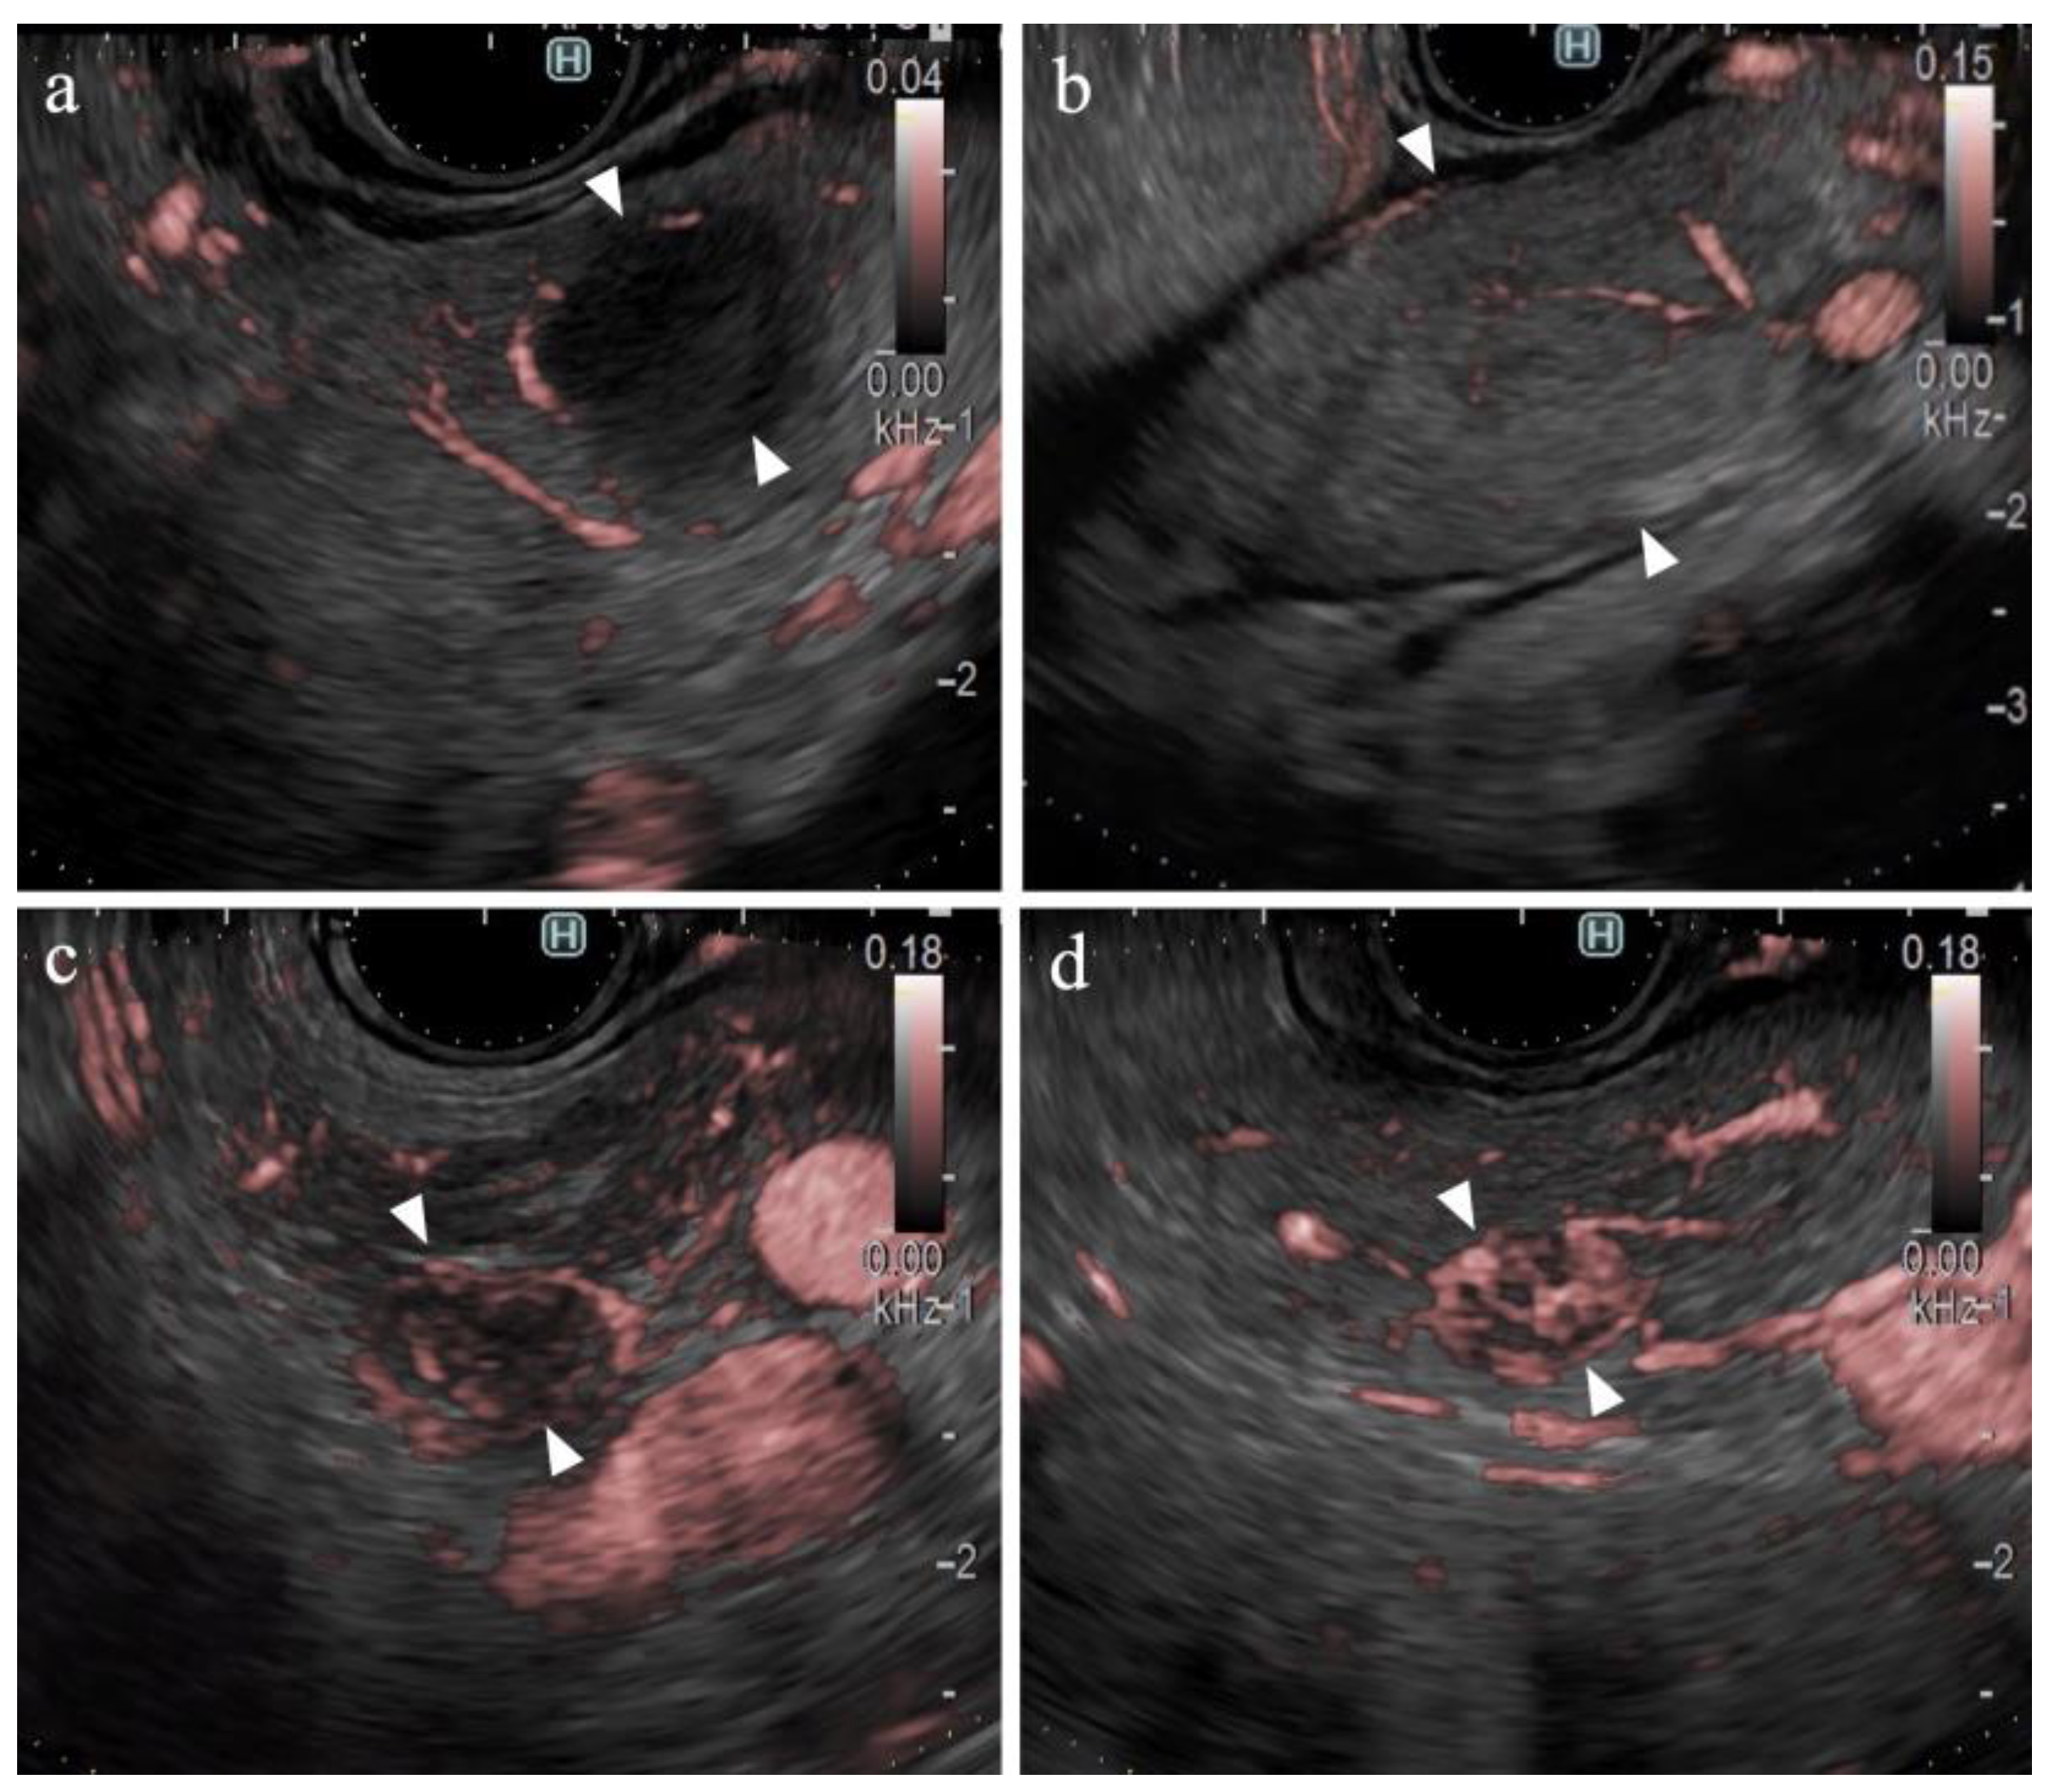

Figure 4.

Vessel images of DFI. (a) Pancreatic cancer; (b) mass-forming pancreatitis; (c) neuroendocrine neoplasm; and (d) metastatic tumor (renal cell carcinoma). The arrowheads in each figure show the margin of the SPLs.

Table 2 presents the result of the univariate analysis of the characteristics and findings of pancreatic cancer and other lesions. Pancreatic cancer was observed significantly more frequently in the pancreatic head (54%, p = 0.013) and in areas deeper than 25 mm (63%, p = 0.042). The number of large SPLs (>20 mm) was greater in patients with pancreatic cancer than in other types of pancreatic lesions; however, the difference was not statistically significant. The majority of lesions were classified as hypoechoic lesions on B-mode (98% (102/104), p = 0.473). The borders were “well-defined” in 70% of the pancreatic cancer lesions and 81% of other types of lesions (p = 0.362). “Irregular contour” and “heterogenic internal echo” were observed in 88% (73/83) and 83% (69/83) of pancreatic cancer lesions, respectively (p < 0.01). eFLOW detected the presence of vessels in 27% (28/104) of lesions only. The shape and distribution of the vessels were classified in cases where vessels were present within the lesion; however, no significant differences were observed. DFI detected the presence of vessels in 96% (100/104) of the lesions. Thus, the detection rate of DFI was significantly higher than that of eFLOW (p < 0.01). Four lesions without vessels were classified as “hypovascular”. Hypovascular lesions were significantly more frequent in patients with pancreatic cancer (p < 0.01). The distribution and shape of the vessels were evaluated in 100 cases wherein the vessels were present within the lesions. Peritumoral and spotty vessels were significantly more frequent in pancreatic cancer lesions (84% [66/79] and 86% [68/79], respectively; Figure 4a) than in other types of lesions (38% [8/21] and 43% [9/21], respectively; p < 0.01).

3.6. Findings on Lesions Other Than Pancreatic Cancer

Table 4 presents the findings in the NEN (n = 6) and MFP (n = 9) groups. No significant differences were observed between the two groups in terms of lesion characteristics. All lesions were hypoechoic on B-mode. No significant differences were observed between the B-mode and eFLOW findings. DFI could visualize vessels within the SPLs in all lesions. Notably, 83% (5/6) of the NEN lesions were hypervascular, whereas all MFP lesions were hypovascular (Figure 4b), with a statistically significant difference (p < 0.01).

The findings of this study demonstrate the utility of DFI for purposes other than the differential diagnosis of SPLs. DFI enabled the identification of small hypervascular lesions within 10 mm, which was unexpected (Figure 4c,d). The frame rate of DFI is higher than those of B-mode and eFLOW; thus, DFI can be used as a screening evaluation for patients with Multiple Endocrine Neoplasia type 1 or von Hippel–Lindau disease [41,42]. Hypersensitivity to vascular structures aided the avoidance of thick vessels during the EUS-FNB procedure (Figure 5). DFI, rather than eFLOW, can be used to define the vessels more precisely in patients with NEN. This technique enables the effective acquisition of tissue samples without major bleeding. The absence of linear vessels in pancreatic cancer lesions can aid the detection of tumor margins (Figure 6). A pancreatic cancer lesion without a detectable margin was observed on B-mode and eFLOW in this case, and the initial EUS-FNB result was a false negative. Subsequently, DFI was performed, and the normal vessels in the surrounding pancreatic parenchyma near the tumor margin disappeared. The diagnosis was confirmed by puncturing the areas without vessels on DFI. Thus, DFI can be considered a novel tool for determining the differential diagnosis of pancreatic cancer in the future.